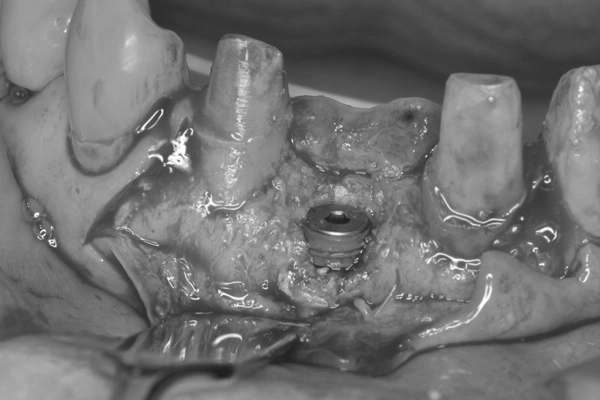

仮歯の装着

インプラント体埋入してから6ヶ月経過後、メンブレンという膜を除去し歯肉が癒えてから唇側歯肉の厚みを増す術式でインプラント2次オペを行い単独歯の仮歯を作製し、装着しました。

前歯の矯正治療

上顎と下顎の前歯の叢生(ガタガタした歯並び)の改善、左上2番の歯列改善のため右上3番〜左上3番、右下3番〜左下3番に唇側ブラケットを装着し歯列改善を行いました。

上顎はインプラントをアンカー(支点)として唇側傾斜、移動させ、下顎は右下1、2番と左下1、2番を中間地点くらいに移動させました。